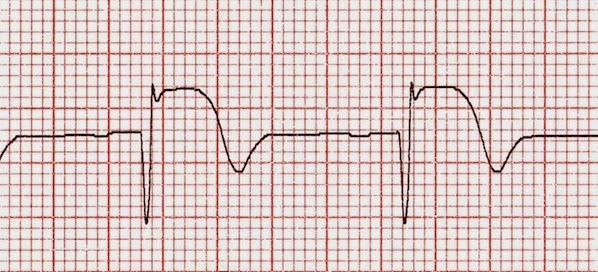

Fibrinolíticos para el infarto de miocardio: ¿cuál elegir?

En entornos donde la reperfusión mecánica primaria no es accesible, el uso de fibrinolíticos sigue siendo la mejor opción en el infarto de miocardio con ST elevado. Esta revisión compara la eficacia y seguridad de las alternativas disponibles. The Lancet, 19 de agosto de 2017